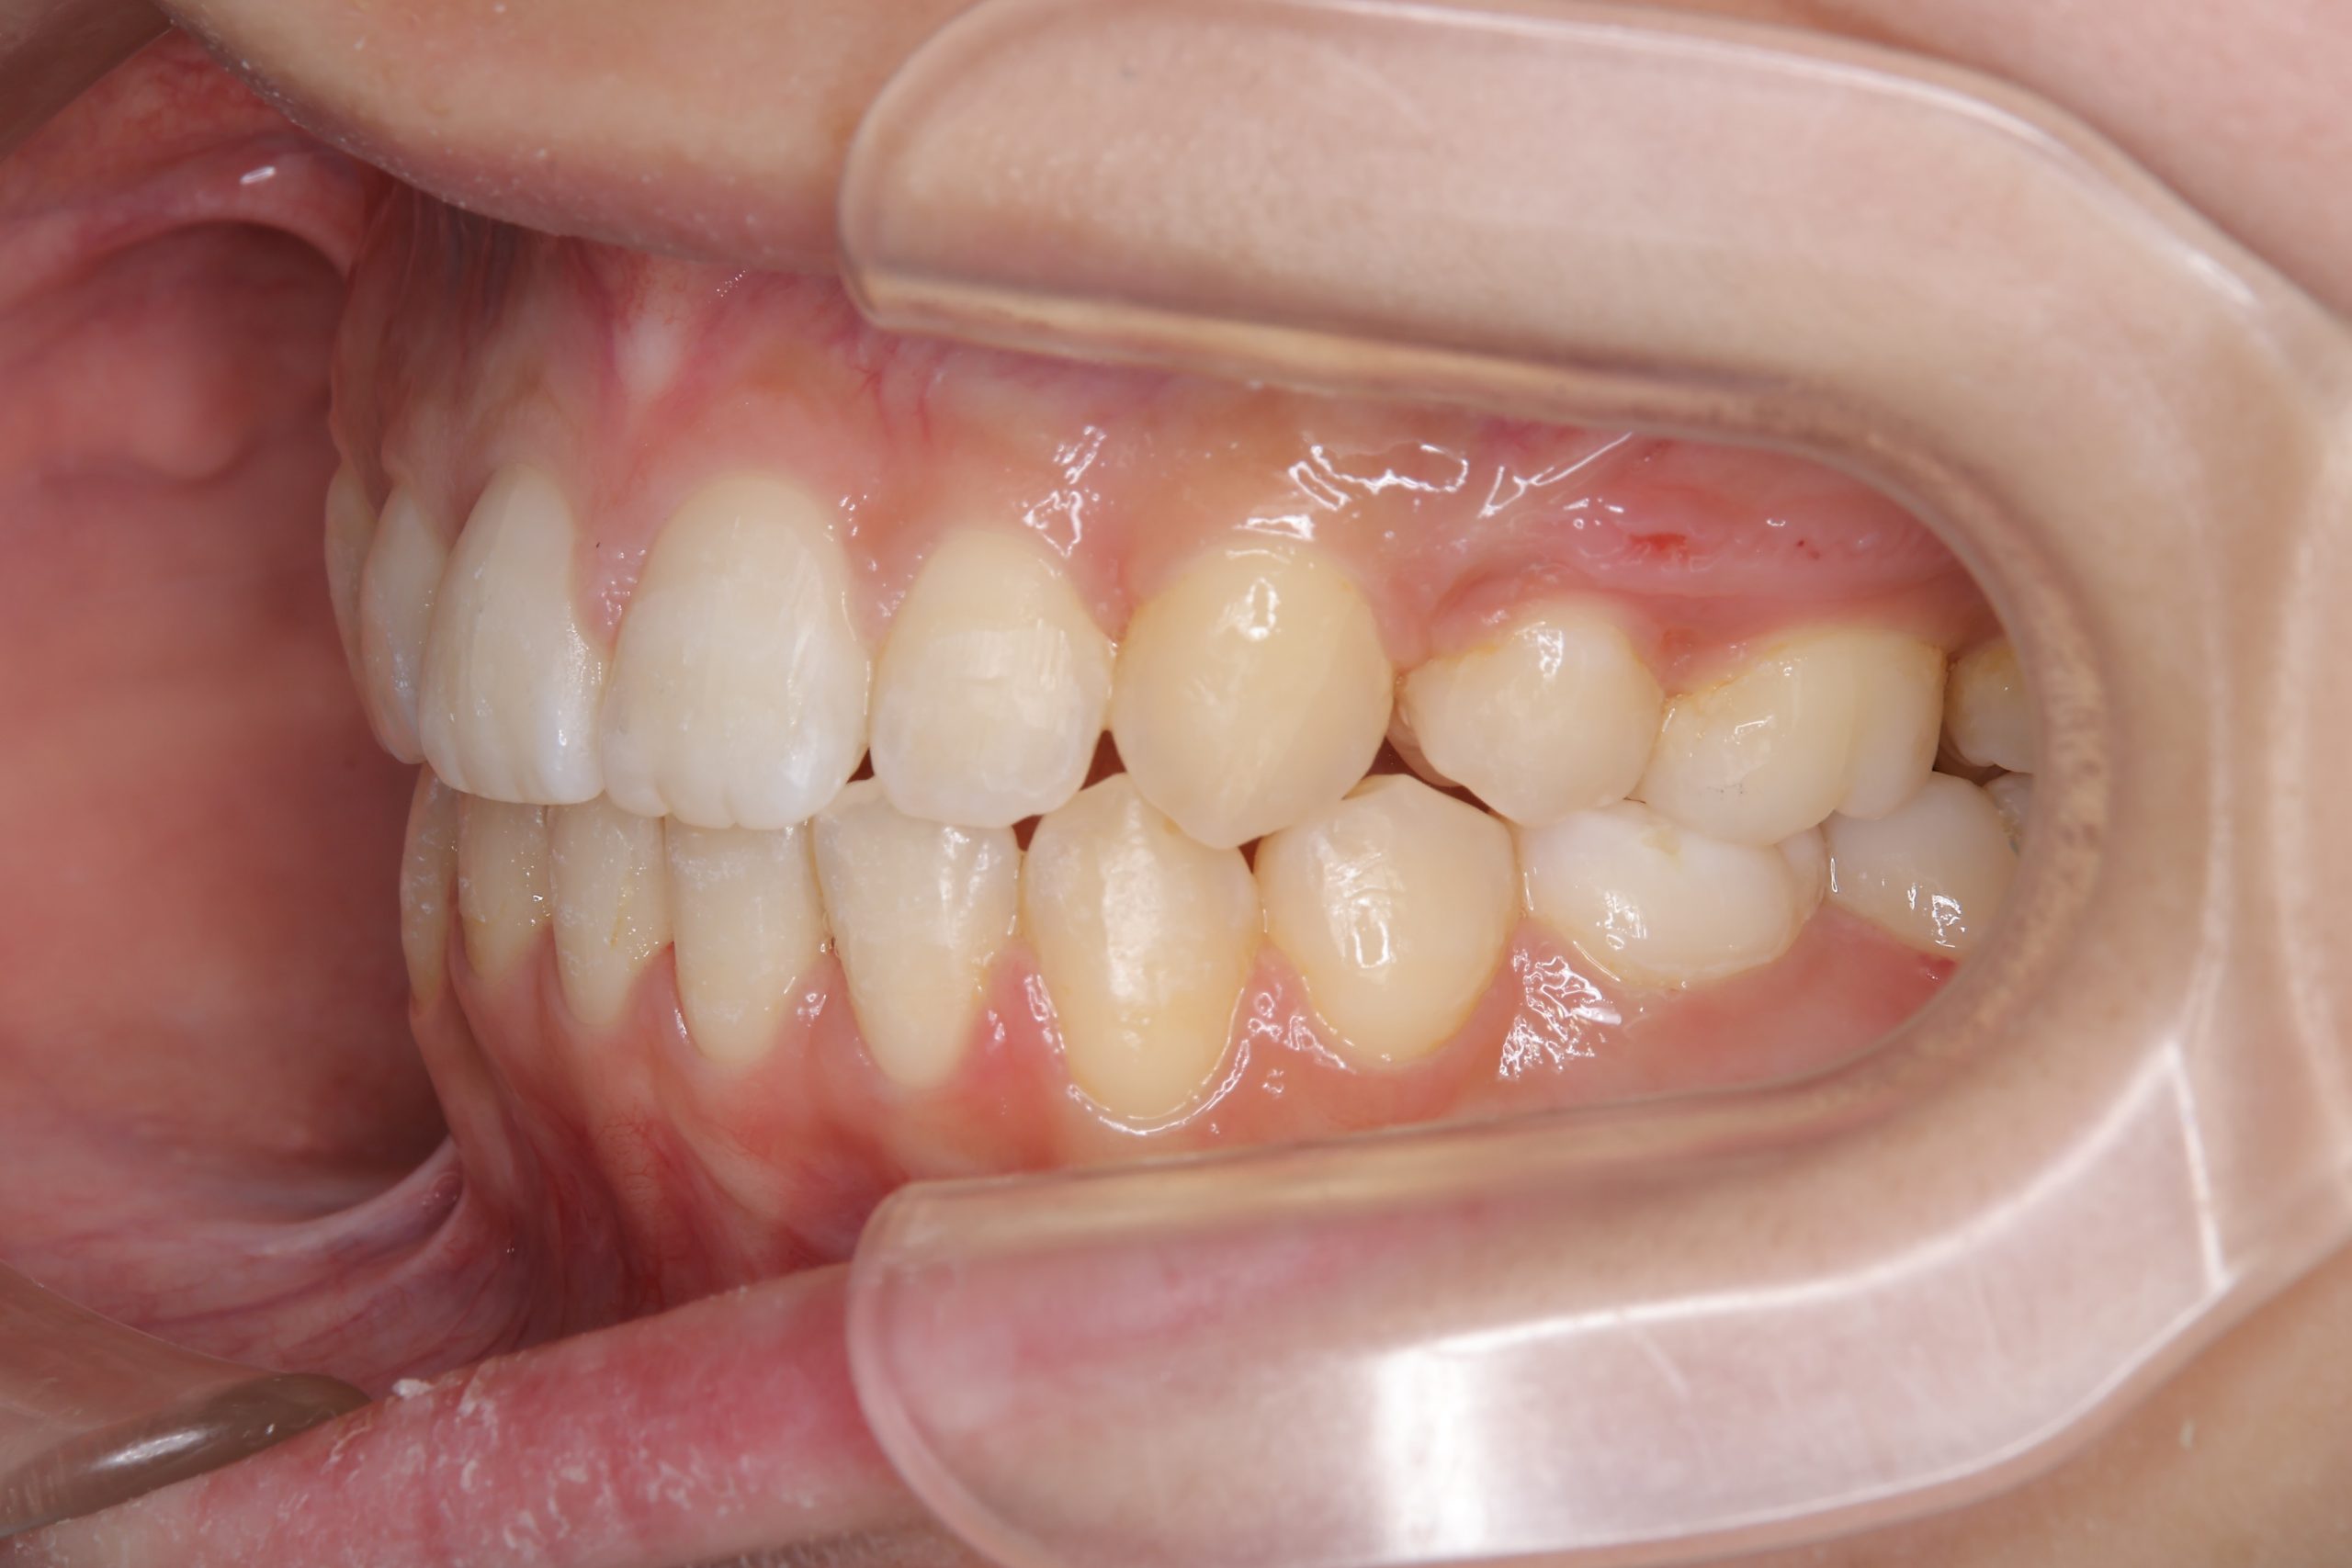

ビフォー

全顎ワイヤー矯正 症例_418

主訴 歯並びがガタガタ ※抜歯あり

施術内容 成人矯正1期治療

治癒期間 2年10か月間

費用 1,069,200円(税込)